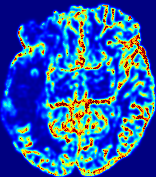

4.3.1 Advection Imaging via Advection-Diffusion

Slice #1Slice #2Slice #3Slice #4Slice #5Slice #6𝐕gt𝟐subscriptnormsuperscript𝐕gt2\|\bf{V}^{\text{gt}}\|_{2}Refer to captionRefer to captionRefer to captionRefer to captionRefer to captionRefer to caption𝐕est𝟐subscriptnormsuperscript𝐕est2\|\bf{V}^{\text{est}}\|_{2}Refer to captionRefer to captionRefer to captionRefer to captionRefer to captionRefer to captionRefer to caption1.51.51.51.21.21.20.90.90.90.60.60.60.30.30.30.00.00.0(mm/s)𝑚𝑚𝑠(mm/s)Destsuperscript𝐷estD^{\text{est}}Refer to captionRefer to captionRefer to captionRefer to captionRefer to captionRefer to captionRefer to caption0.0150.0150.0150.0120.0120.0120.0090.0090.0090.0060.0060.0060.0030.0030.0030.0000.0000.000(mm2/s)𝑚superscript𝑚2𝑠(mm^{2}/s)

Figure 14: PIANO identifiability testing: advection imaging via advection-diffusion. Top row shows 𝐕gt2subscriptnormsuperscript𝐕gt2\|{\bf{V}}^{\text{gt}}\|_{2} used for simulating ground truth pure advection. Rows below show the estimated 𝐕est2subscriptnormsuperscript𝐕est2\|{\bf{V}}^{\text{est}}\|_{2} and Destsuperscript𝐷estD^{\text{est}} on corresponding slices. Note that the plotted value scale for Destsuperscript𝐷estD^{\text{est}} is 0.01 of that for 𝐕gt2subscriptnormsuperscript𝐕gt2\|{\bf{V}}^{\text{gt}}\|_{2} and 𝐕est2subscriptnormsuperscript𝐕est2\|{\bf{V}}^{\text{est}}\|_{2}.

We use the same ‘Advection Imaging’ simulation of Sec. 4.2.1 as the concentration dataset for PIANO. However, instead of modeling pure advection (Eq. 15), we let PIANO estimate both velocity 𝐕estsuperscript𝐕est{\bf{V}}^{\text{est}} and diffusivity Destsuperscript𝐷estD^{\text{est}} via the advection-diffusion PDE (Eq. 2) underlying the proposed PIANO model. Fig. 14 shows the estimated 𝐕est2,subscriptnormsuperscript𝐕est2\|{\bf{V}}^{\text{est}}\|_{2}, and Destsuperscript𝐷estD^{\text{est}} fields for one patient. Although PIANO has the freedom to estimate both a velocity and a diffusivity field from pure advection, PIANO differentiates well between advection and diffusion: the estimated 𝐕est2subscriptnormsuperscript𝐕est2\|{\bf{V}}^{\text{est}}\|_{2} successfully reproduces the ground truth 𝐕gt2subscriptnormsuperscript𝐕gt2\|{\bf{V}}^{\text{gt}}\|_{2} governing the simulated advection process, just as it already did in the ‘Advection Imaging via Advection’ test (Fig. 12). More importantly, the estimated diffusivity Destsuperscript𝐷estD^{\text{est}} is orders of magnitudes smaller than 𝐕est2subscriptnormsuperscript𝐕est2\|{\bf{V}}^{\text{est}}\|_{2}, indicating the estimated diffusion is negligible compared to the estimated advection, which is highly consistent with the underlying pure advection of the simulated data.